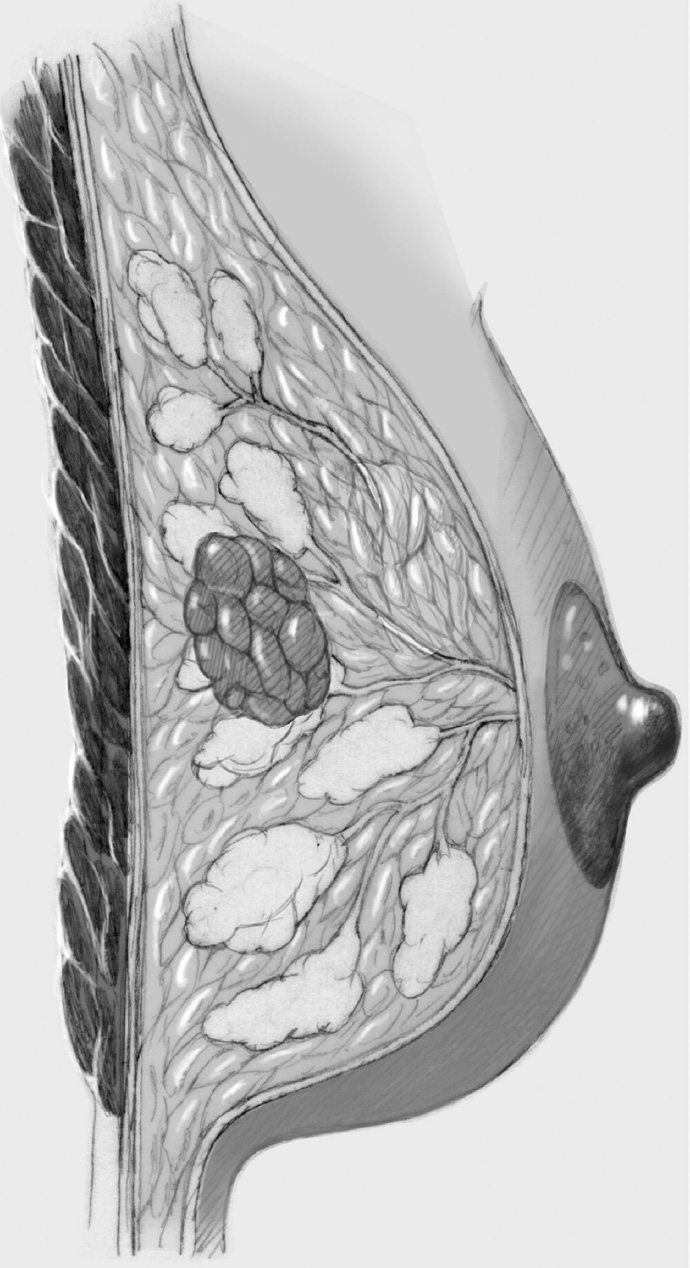

Complex and Oncoplastic Breast-Conserving Treatment

The same principles apply as in simple breast-conserving treatment though the size of the tumor necessitates more extensive segmental resection or even quadrant resection, which requires internal breast reconstruction with more complex defect cover by lobes of the breast. Often, more skin has to be resected to match the reduction in the size of the breast produced by the operation. Only the last step of periareolar de-epithelialization and nipple repositioning—that is, complex oncoplastic breast-conserving treatment—is not performed.

The skin is incised over the tumor region as far as possible (depending on surgeon, tumor size, tumor location, and subsequent treatment). A radial incision may be useful for tumors located in the lower quadrants or directly in the axillary tail of the breast. If the tumor is just beneath the skin, an island of skin over the tumor should be resected also. This can be achieved with both an elliptical semicircular incision and a radial incision. Another form is a purely periareolar incision when the tumor is in a relatively central position (see illustrations below).

The segment containing the tumor is dissected sharply with dissecting scissors or electrocautery; an adequate initial resection margin should be obtained under digital control or sonographic direct visualization. A specimen sonogram or mammogram is performed when needed.

After complete resection of the tumor area, a drain is placed in the wound cavity.

The former tumor region is marked with titanium clips (usually three clips for spatial orientation).

The adjacent parenchyma is mobilized subcutaneously so that the defect can be filled with lobes of breast tissue. Mobilization means exposing the breast relative to the skin or muscle to achieve adequate mobility of < 25% or > 25% as required.

Tension-free approximation for complete intramammary cover of the defect

The wound is closed in two layers, suturing the skin with an absorbable monofilament (3–0 or 4–0) suture.

Special Technique Simple, Complex, and Oncoplastic Breast-Conserving Surgery